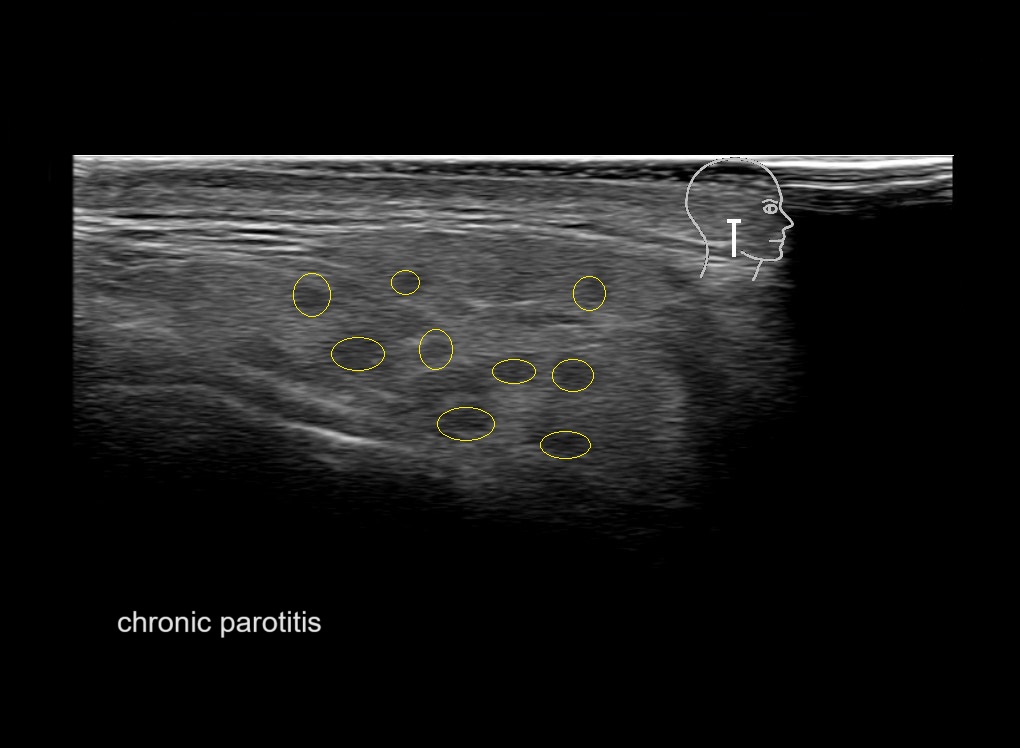

With ultrasound signs of inflammation can be visualized. Edema can be seen as a hyperechoic appearance of the subcutaneous fat, sometimes separated by hypoechoic fluid filled area’s, known as cobblestone appearance. Increased vascularization (hypervascularity) can be seen on colour Doppler. An abscess will appear as a fluid collection appearing as an irregular hypoechoic area with heterogeneous internal echoes and a thickened wall. Posterior acoustic enhancement can be present, and there is vascularity around but not within the mass. Under ultrasound guidance, abscesses can be managed by needle aspirations (18G) under antibiotic cover.